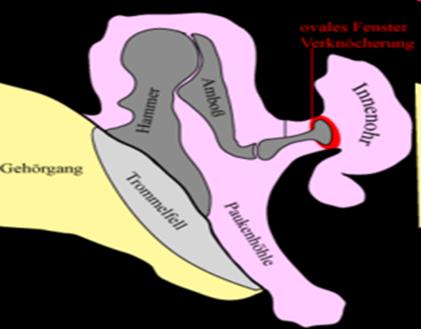

Die Otosklerose ist eine Erkrankung des Knochens, der das Innenohr umgibt (Labyrinthkapsel).